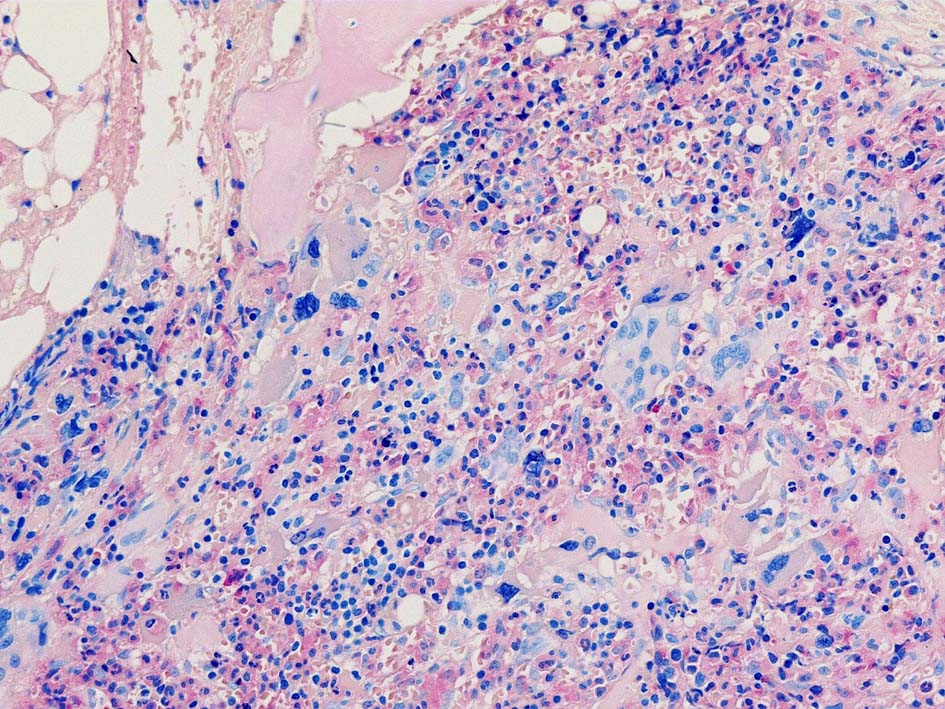

Case02; Meylofibrosis, overt fibrosis

77year-old female. 40歳時polycythemia veraと診断されていた.

[注] この症例は詳細は不明であるが, 過去にPVと診断されているため, PVに伴う二次性のmyelofibrosisの診断になる.

黒染する弾性線維の増生のほか, 赤く染まる膠原線維の増生が確認される. MF-2 fibrosis. 鍍銀染色の核染色をすると膠原線維の赤染がわからなくなるので行わない.